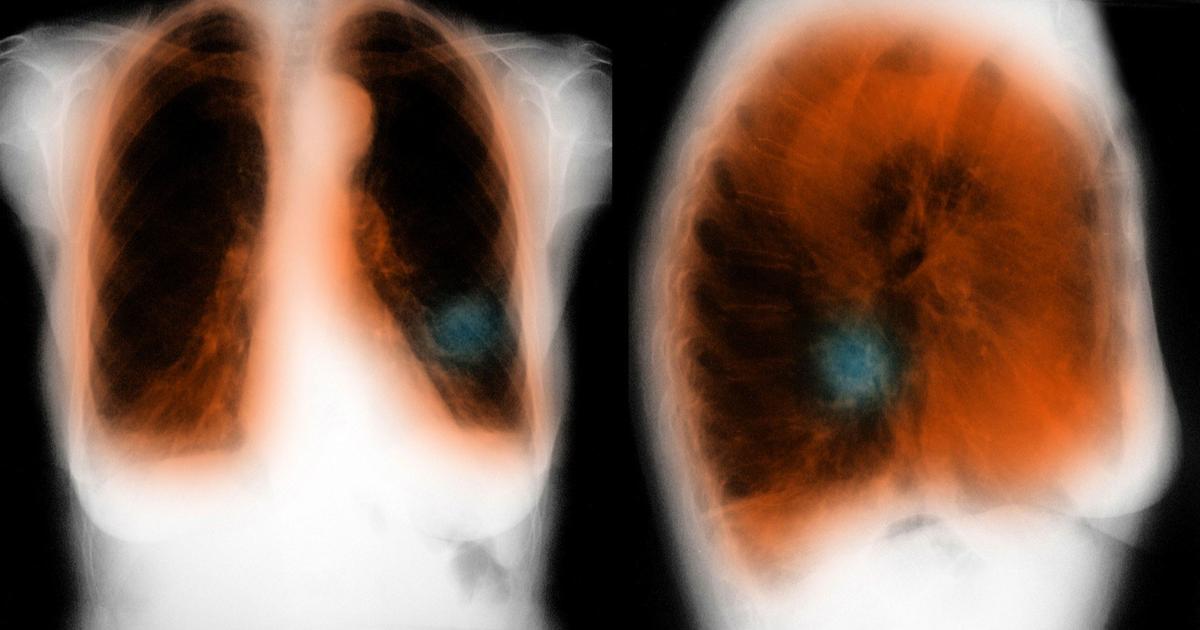

Влияние вейпа на легкие: Фотографии и исследования

Раздел: Визуальный дайджест